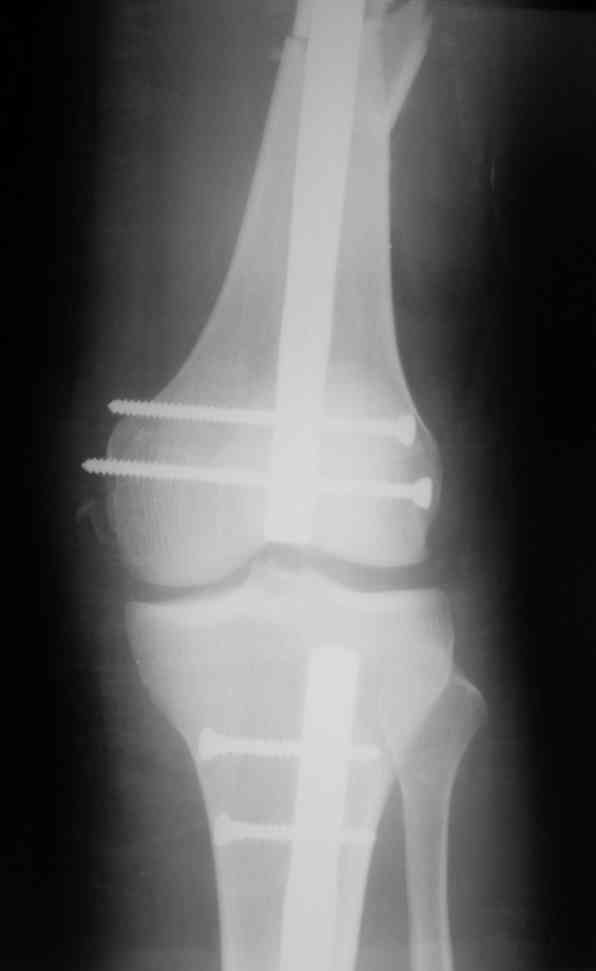

Дорогой Александр. Имею скромный опыт использования системы Fixion при переломах плеча, бедра и тибии. Всего 18 наблюдений с сентября 2006 г. Результаты отличные. Гвоздь индивидуален для каждого медуллярного канала. Легко имплантируется как в узкий, так и в деформированный канал. Это позволяет применять метод интрамедулярного остеосинтеза без ненужных потерь времени операции, флюороскопии и реально снижает крвопотерю и операционный риск. Удаление происходит без проблем. Особенно интересны больные с ипсилатеральными переломами бедра и голени.

В отношении ранней нагрузки при спиральных переломах лучше не торопиться. По данному случаю необходимо достигнуть исчезновения щели между штифтом и внутреним кортексом по Rg. А так картинка прекрасная - и длина сегмента и репозиция. Можно поздравить, коллега!